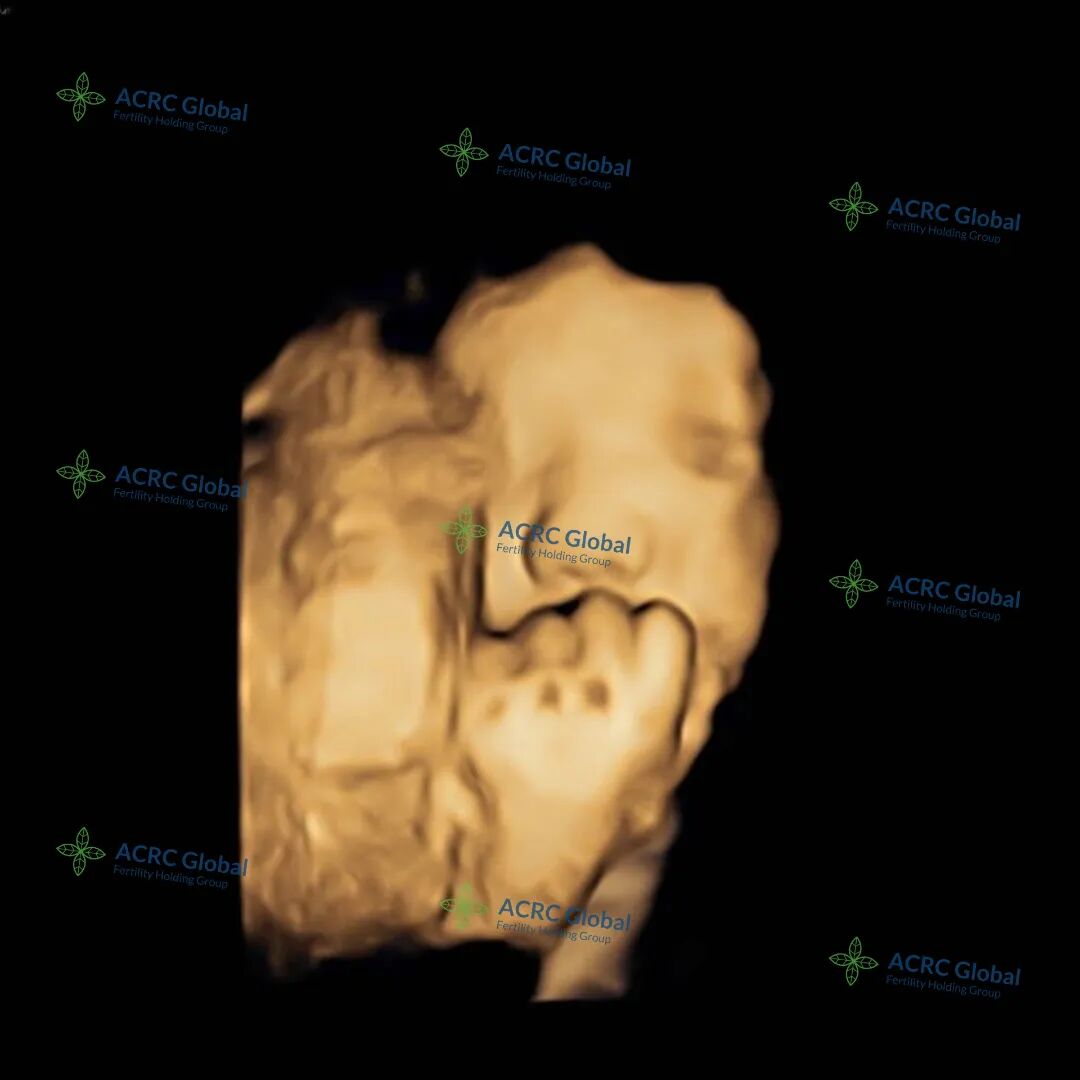

爱妈E的三维B超显示,宝宝已经37周了,体重达到六磅多,已经足月,小脸蛋看上去圆润饱满、十分可爱。虽然小手轻轻挡住了脸蛋,但从侧脸的轮廓中依然可以看出她那精致的小公主模样。医生预估,宝宝在出生时将会有七磅左右。准父母已经满怀期待地准备迎接宝宝的到来,期盼着和她的第一次见面呢!